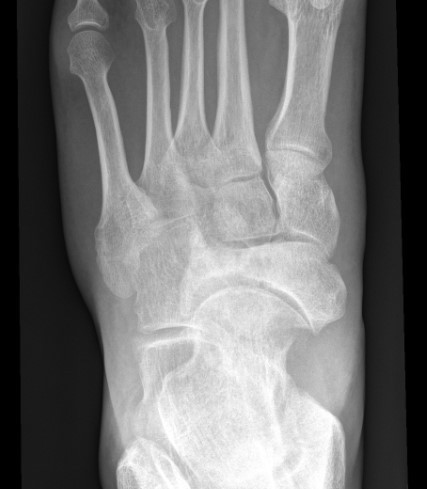

Xray

Sclerosis / Fragmentation

Talonavicular osteoarthritis

Talocuneiform osteoarthritis

Midfoot collapse